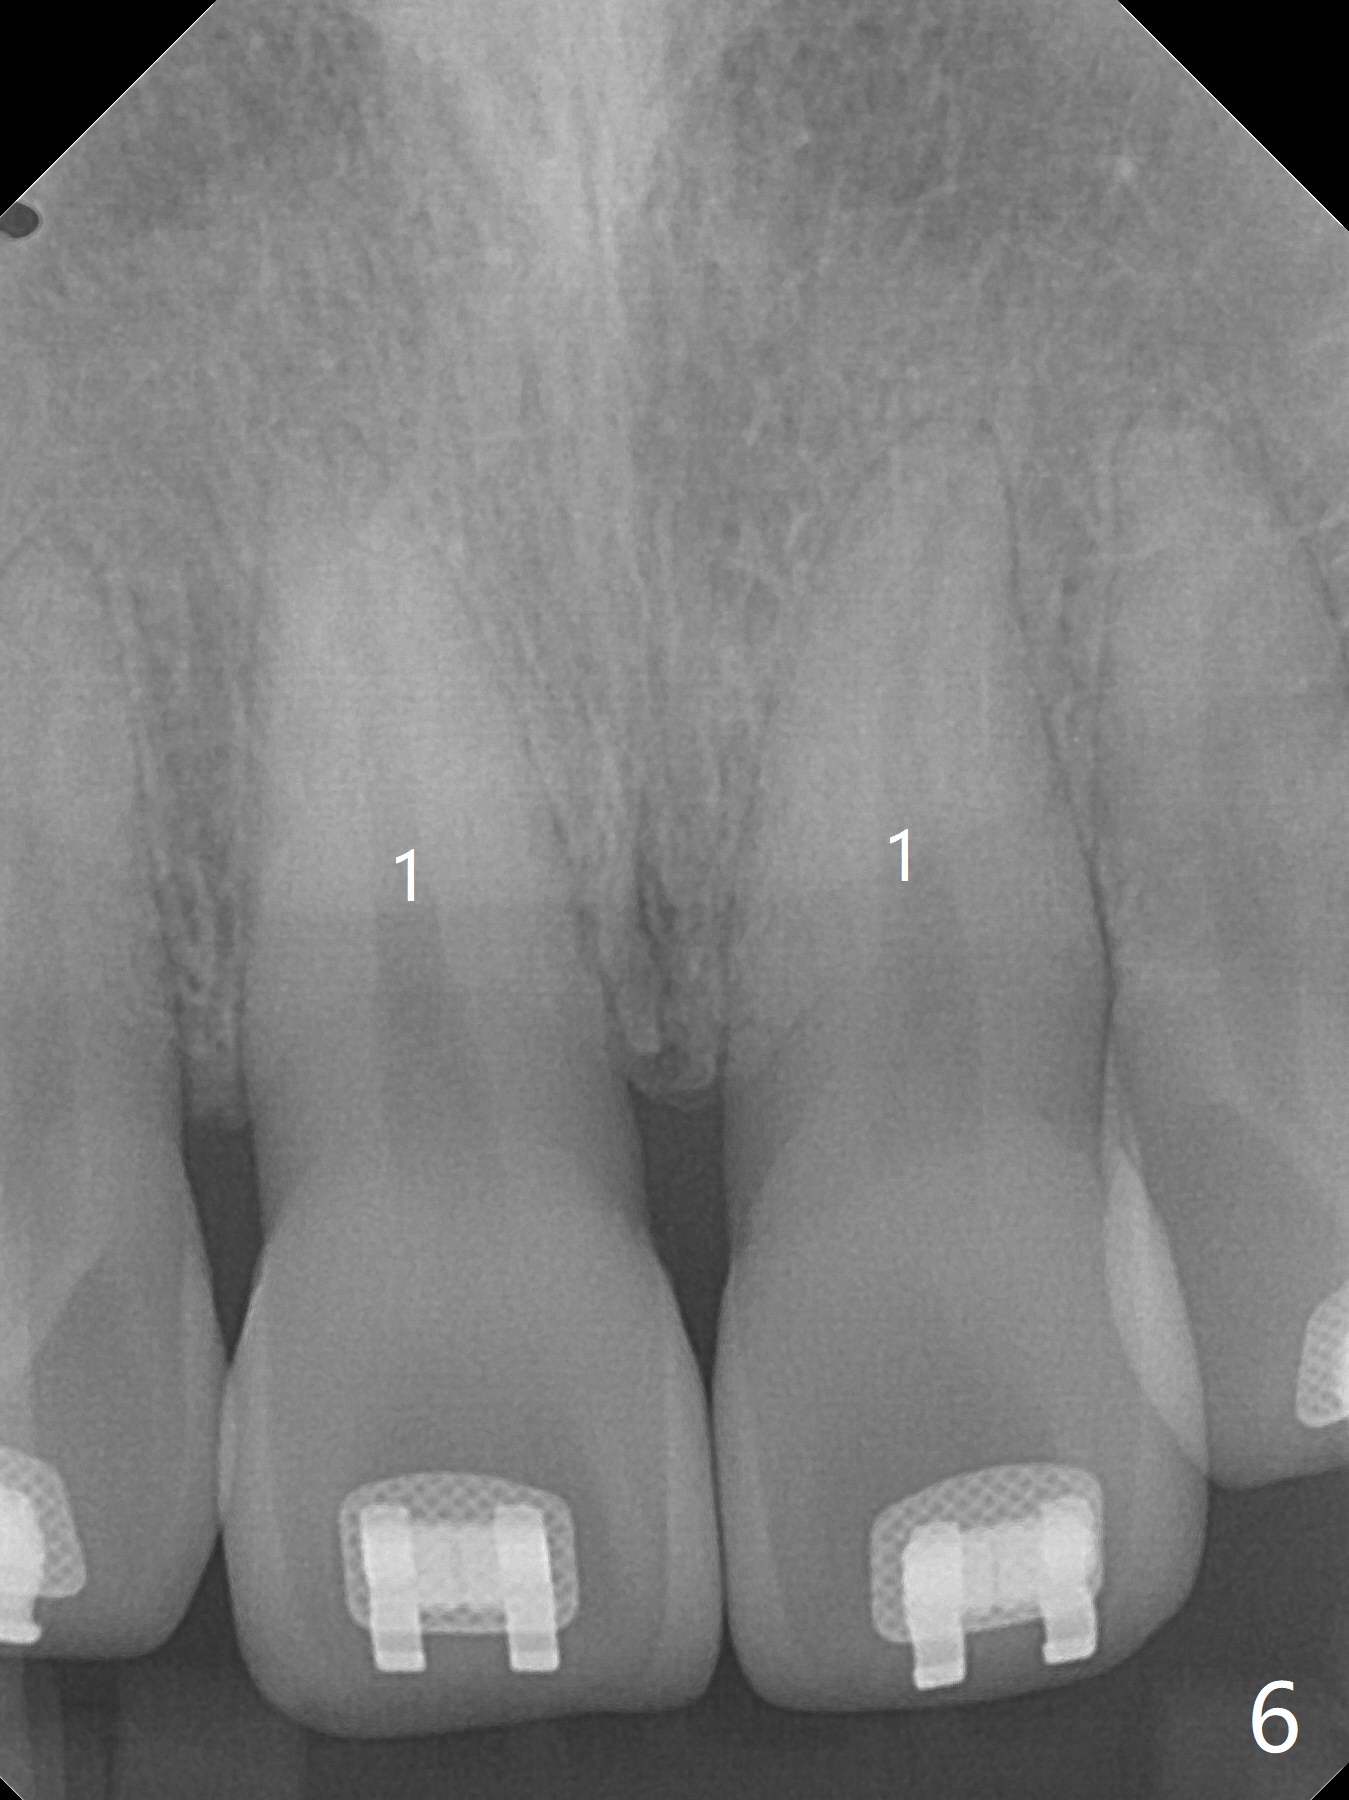

A 40-year-old man requests orthodontics after #17 and 32 extraction. UL5 is missing (Fig.1), while the upper midline deviates to the left (Fig.2 arrow) with crowding between UL2 and 3 (Fig.3). The main goal is to retract UL5 distal and move the upper midline to the right to alleviate UL anterior crowding. Implant will be not needed. To monitor potential root resorption associated with tooth movement, preop PAs are taken (Fig.4-7). The space for an implant at UR5 is narrow. UR4 needs to be distalized using UR7 or a miniimplant distal to UR7 as an anchor (Fig.8). UR4 and 3 will be repositioned to establish Class I occlusion (Fig.9). The space gained by UR4 distalization may be enough to correct the upper midline deviation and UL3 malposition (Fig.10). Brackets will be placed in the lower arch in spite of the normal alignment (Fig.11). UL2 and 3 brackets are unable to be engaged to 14 niti wire (Fig.12). Next visit try to engage UL2 bracket. If not, save the old wire for possible future reuse. Closed spring is placed with 18 ss wire <3 months post banding (coronavirus). Three weeks post closed spring between UR4-7, UR3,4 are being distalized (Fig.13). Distalization of UR4 is not much in 5.5 months (Fig.14,15). It seems necessary to use a miniimplant distal to UR7 as an anchor (Fig.16 white circle), place a long hook mesial to UL4 (more or less root movement instead of tilt) and place the same closed spring between the anchor and hook. In spite of the fact that UR4 seems to have been completely distalized and that UR2 is being distalized 8 months post banding (Fig.18), a 8 mm long mini-implant is placed in the maxillary tuberosity with minimal local anesthetic (Fig.17,19). A longer closed spring (18 mm) is placed between the implant and UR3 hook (Fig.20). Next appointment a lingual button will be placed at UR4 for rotation, while a post hook mesial to UR3 for torque. UR3 distalizes with the help of UR mini-implant, which is unfortunately loose. Next visit place lingual button at UR4 (Fig.21 arrow) to distalize the lingual cusp. Crimpable power hook is placed mesial to UR2 for distalization (for root torque, Fig.22). If it works, remove the wire and reposition the hook for UR1 next visit. UR2 is distalized in one appointment (~ 1 month, Fig.23, as compared to Fig.22). With lingual button at UR4, rotation seems to have been corrected shortly (Fig.24 arrow).